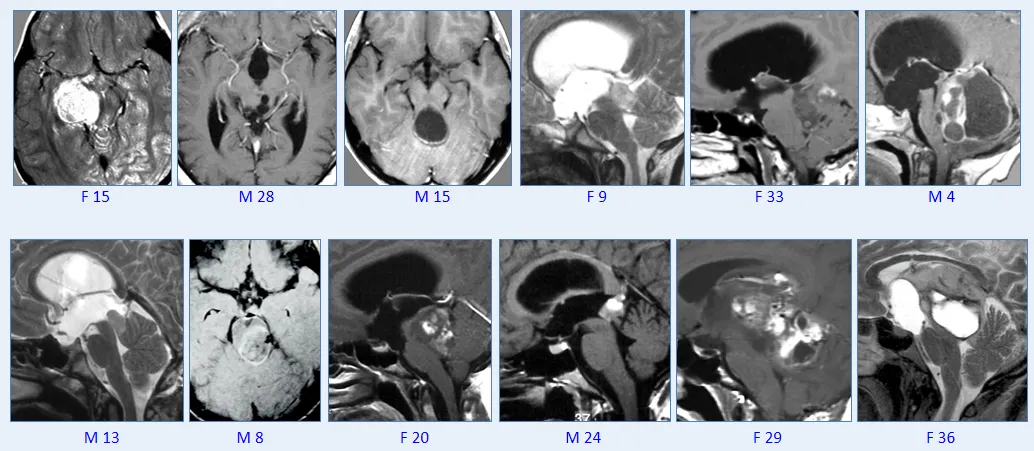

▼巴教授脑干毛星50+例影像图汇

1.脑干不是“无人区”!

2.显微手术在局灶性脑干胶质瘤的整体管理中发挥着重要作用。

3.”低级别“胶质瘤是合适的手术候选者。

4.在许多情况下,可以尝试并实现治愈。